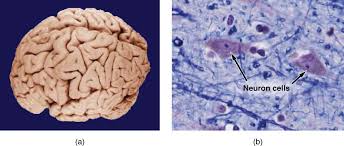

47+ Difference Between Anatomy And. Simply put, anatomy is the study of the structure and identity of body parts, while physiology is the study of how these parts. Anatomy and physiology are two related biology disciplines.

Anatomy vs physiology when it comes to biology, anatomy and physiology are topics that you would often come across with. Both anatomy and physiology have been studied for centuries. Anatomy and physiology are probably 2 of many different sciences necessary for the best understanding of the human body and how it functions. The difference between anatomy and physiology.